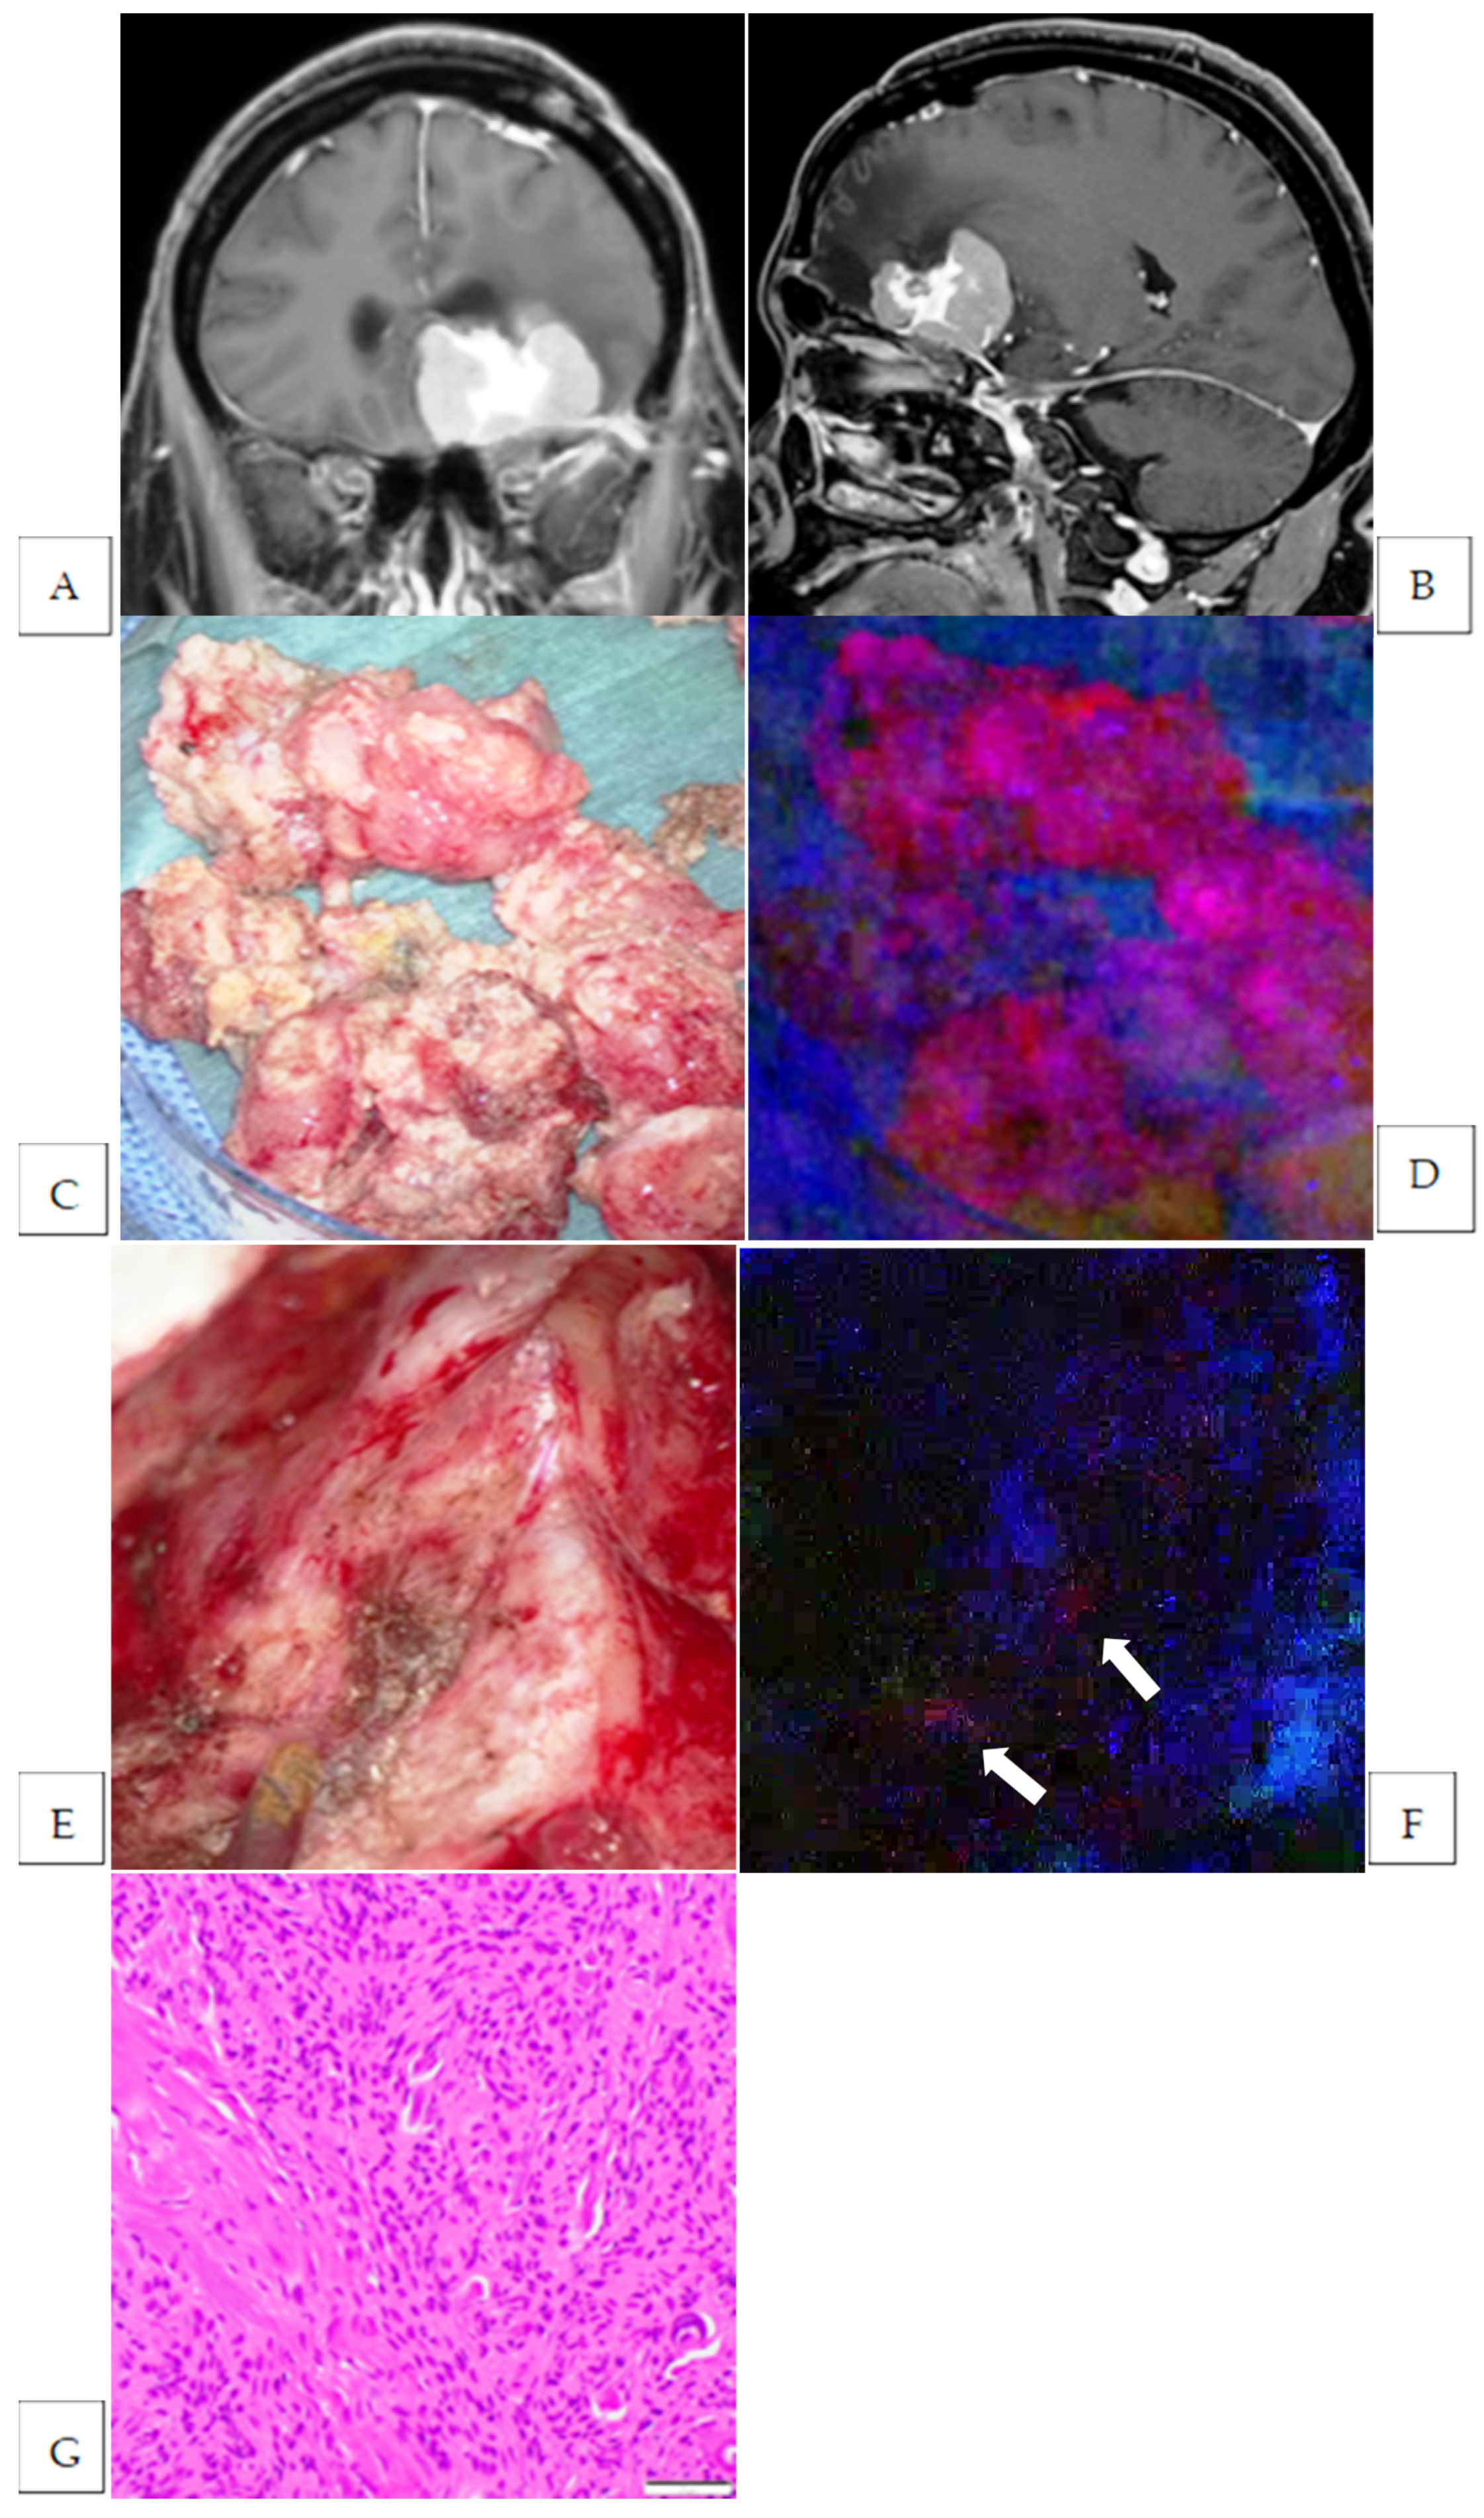

3. Results